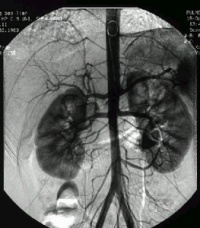

或椎基底动脉。动脉局部的弹力层和肌层变弱,而突出为瘤,一般在1cm以下。临床症状主要是急性蛛网膜下腔出血、脑实质出血或脑室内出血。未破裂之前则常被忽视,可有头痛及局部压迫症状,特别是颅神经麻痹。家族性囊性动脉瘤常为多发。本病也常伴全身病和其他血管病,如AVM、主动脉缩窄、多囊肾、烟雾病等。MRI和MRA可助诊断,但血管造影更为可靠。本病还应与获得性脑动脉瘤鉴别,如外伤性、感染性等。本病易有复发性出血,故应手术治疗。

多见于大脑半球,为密集的薄壁血管。儿童期常无症状而被偶然发现。一般到年长儿或成人才出现症状,主要是癫痫、头痛、脑内出血。CT可见桑椹状病灶。MRI的T2相显示中心明亮而围绕以暗环的影像。常见家族性病例,为显性遗传。本病也可见视网膜、肝、肾、皮肤的相似海绵状血管瘤。对于出血危俭性不大的病例可先观察,必要时手术。